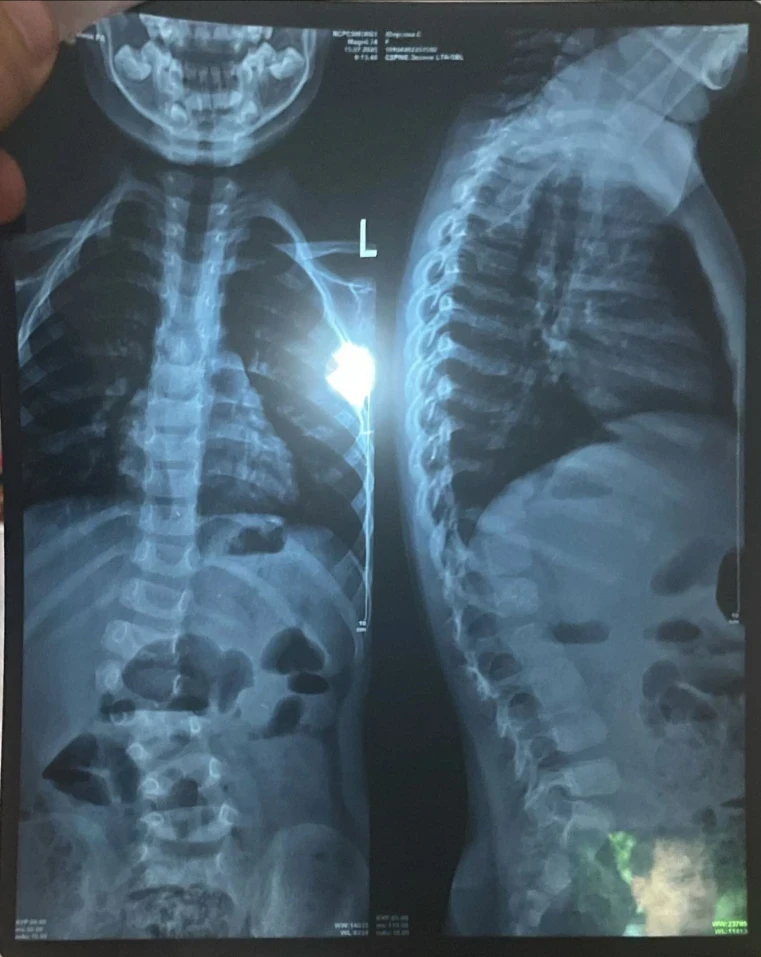

У девочки выявили сколиоз сложной формы, что вызывает у неё затруднения при ходьбе и беге, и она вынуждена проводить большую часть дня в сидячем или лежачем положении.

«Узнав, что ничего не помогает, мы обратились за консультацией к турецким профессорам. Они заявили, что единственный выход — операция, и чем быстрее она будет проведена, тем лучше для роста и развития Сумаи. Кроме того, мы узнали, что у неё есть лишняя кость на позвонке, что также является последствием сколиоза», - сообщает мама.

Сколиоз уже вызвал асимметрию тела, у Сумаи одно плечо ниже другого, а одна нога короче.

«Мы не знали, что сколиоз может привести к таким серьёзным последствиям, пока не столкнулись с этим сами. Мы проходили обследования, стараясь, чтобы дочь росла и развивалась нормально. Но о том, что искривление позвоночника может сдавливать внутренние органы и вызывать сильные боли, мы даже не подозревали. Поэтому нам нужно спешить с операцией», - добавляет Мадина.